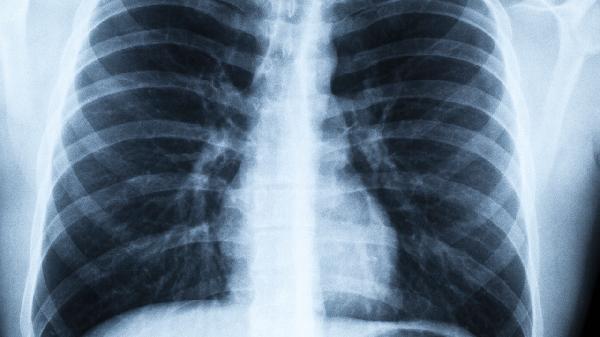

病毒性肺炎是由病毒感染引发的间质性炎症,主要表现为肺泡壁出现水肿和充血,同时伴有淋巴细胞的浸润。而化脓性炎症则是由细菌感染引起的,特征是中性粒细胞聚集并伴随脓液的形成,两者在病原体种类和病理表现上存在明显差异。